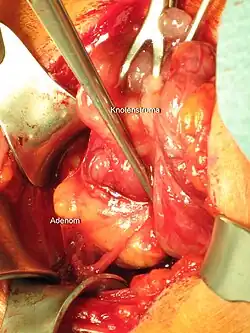

![]() Parathyroidectomy for parathyroid adenoma | |

The patient is placed in a semi-Fowler position and the neck is extended. An abbreviated Kocher incision is made and the platysma muscle is dissected horizontally. The strap muscles are released off of the thyroid gland. Then the thyroid gland is mobilized and the parathyroid arterial blood supply is suture ligated. The entire parathyroid adenoma is identified and dissected out. Intraoperative PTH monitoring can begin at this time and will show falling PTH levels if the entire adenoma has been resected.[5]